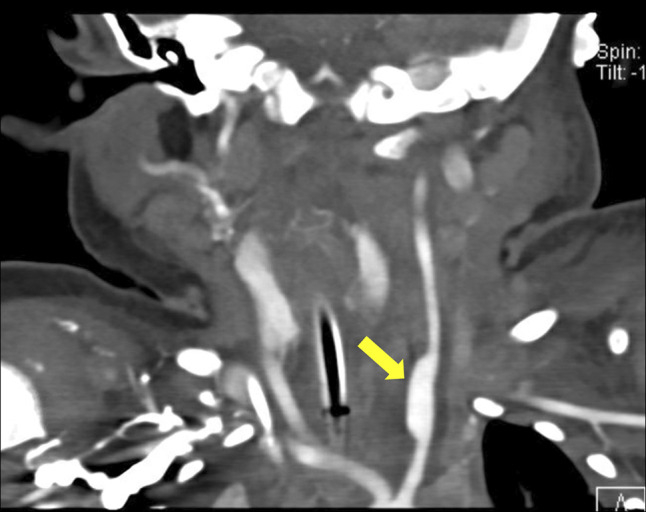

纽扣电池误食是小儿异物急诊的重要原因,往往会导致严重的并发症。我们提出的情况下,一个婴儿谁发展左总颈动脉食管瘘后纽扣电池摄入,这是进一步复杂的假性动脉瘤的形成。通过随访影像确诊,假性动脉瘤成功使用分流支架治疗。患者保持临床稳定,无神经功能障碍。这一病例强调了早期诊断和干预对预防出血和中风等危及生命的并发症至关重要。此外,它强调了随访影像学研究的必要性,即使在无症状的患者中,也可以监测延迟并发症并告知正在进行的治疗。

Button battery ingestion is a significant cause of pediatric foreign body emergencies, often leading to severe complications. We present the case of an infant who developed a left common carotid-esophageal fistula after button battery ingestion, which was further complicated by the formation of a pseudoaneurysm. The diagnosis was confirmed through follow-up imaging, and the pseudoaneurysm was successfully treated using a flow diversion stent. The patient remained clinically stable without neurological deficits. This case underscores the critical importance of early diagnosis and intervention to prevent life-threatening complications such as hemorrhage and stroke. In addition, it highlights the necessity of follow-up imaging studies, even in asymptomatic patients, to monitor for delayed complications and inform ongoing management.